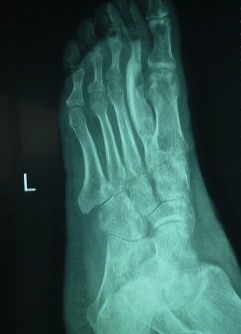

Postoperative recovery was uneventful, and early hand physiotherapy commenced 2 weeks after wound healing was achieved. In the 1-year follow-up, the thumb and thenar eminence had healed well with no concerns regarding wound healing nor scar appearance (Figure 10). Sensation was restored with light touch and 2-point discrimination being present. Active movements, such as MCPJ extension and a hook grip, were restored (Figure 11). A radiograph showed the first carpometacarpal joint in a good position with the fracture having healed without any bone resorption (Figure 12). The iliac crest bone graft used to reconstruct the second metatarsal had also healed well (Figure 13).